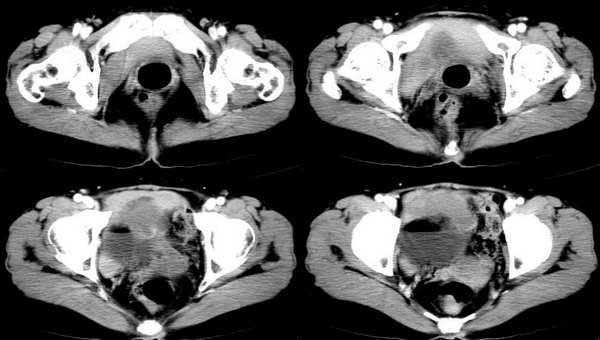

女,55岁,因下腹胀痛2月,b超发现盆腔包块7天,而入院,检查:右侧附件如女拳头大小包块,活动差,轻压痛,质中,子宫稍正常缩小,彩超示子宫4.9cmx2.6cmx2.3cm ,右侧附件包块示:8.7cmx9.1cmx6.3cm 的混合性回声,脂质分层征

囊性畸胎瘤的液-液征,增强瘤结节强化。

畸胎瘤伴瘤内出血。

畸胎瘤,可见典型脂肪-液体征象。

同意大家畸胎瘤的诊断,但不能排除恶变的可能.

右侧肿块前壁的带状软组织密度影我认为是肠管所致,该部位的小肠肠襻由于受到肿瘤的推移呈水平样排列,这样在ct扫描时相邻的肠壁在某些层面上可以呈现宽带状软组织密度影。

良性畸胎瘤伴出血。